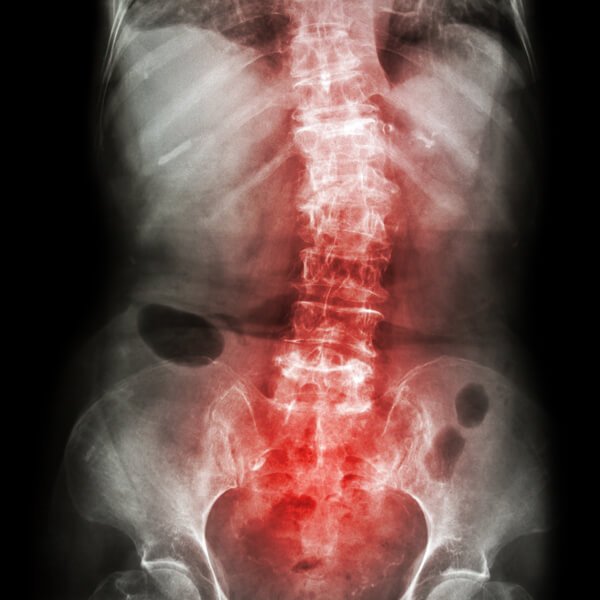

척추측만증

척추측만증은 여러 가지 요인에 의해 일자로 있어야 할 척추가 C자 또는 S자로 휘어진 경우를 말한다. 유형으로는 태아 때 척추 형성 과정에서 이상이 생겨 발생하는 선천성 척추측만증과 원인을 알 수 없는 특발성 척추측만증, 신경계 이상에 의해 발생하는 측만증 등이 있다. 서 있는 자세에서 양쪽 어깨높이가 다르거나 등 뒤 견갑골이 튀어나오면 의심해 볼 만한 질병이다.